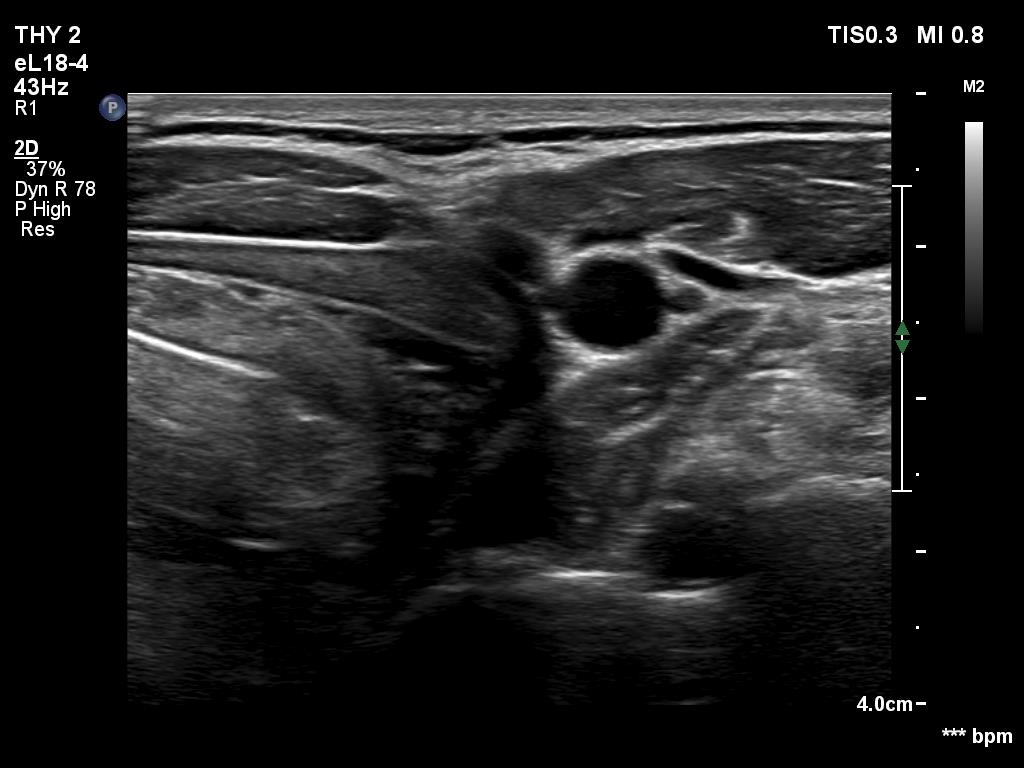

Introduction - case 462 (ultrasonographic picture 12)

Left submandibular area, longitudinal scan.